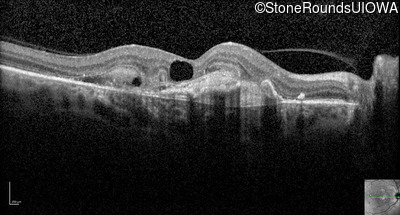

Optical Coherence Tomography - Right - 20/80 +1

Exemplar / OCT Stack

Infrared Fundus Photograph - Right - 20/80 +1